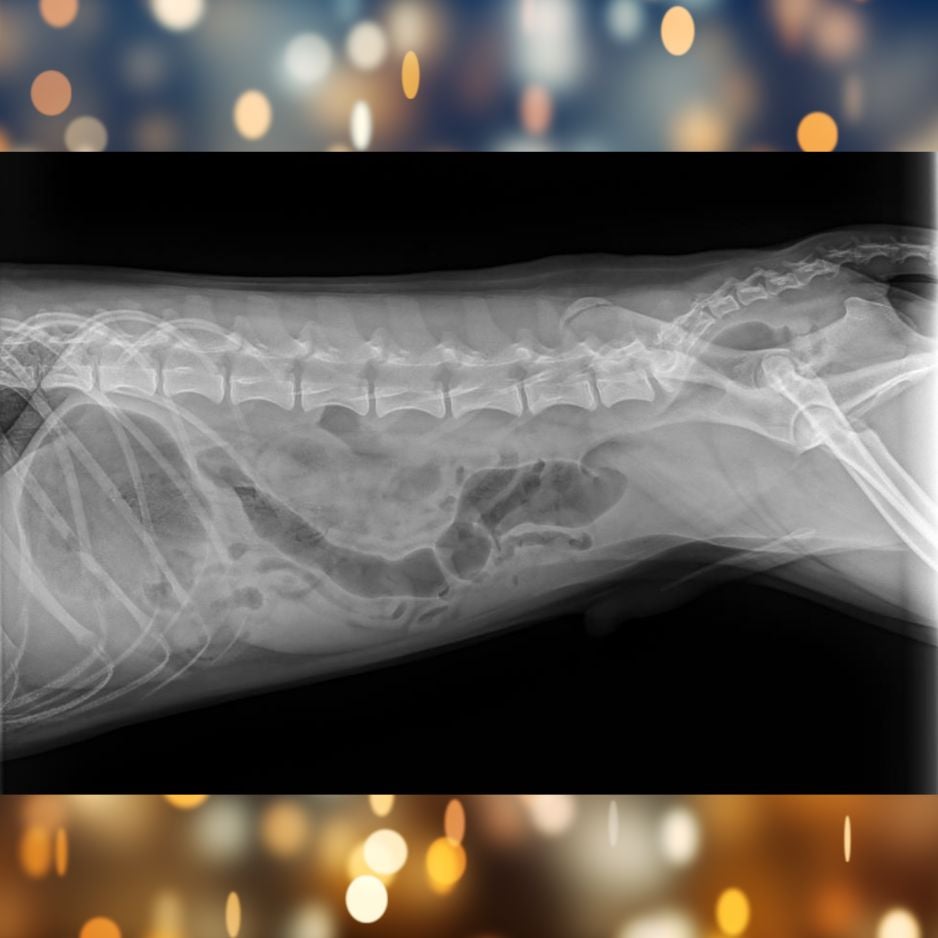

Tito X-rays Day 2

Unfortunately, the material did not move on its own, which meant Tito needed surgery to safely remove the obstruction.